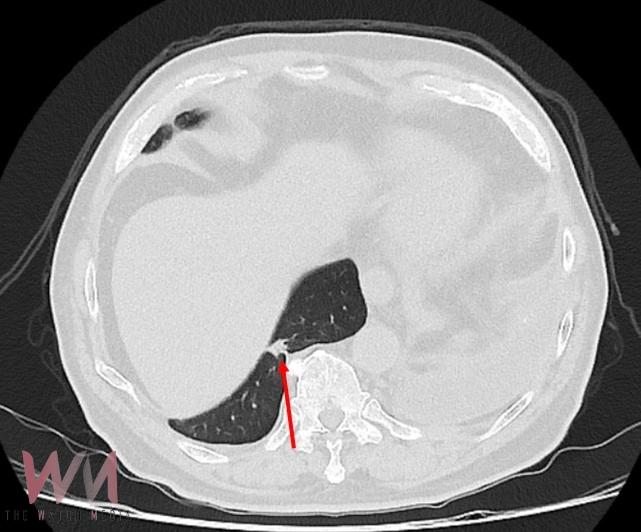

廖啟耀主任指出,仁愛與長庚醫療體系聯盟醫院近年來積極引進達文西機器人手術系統,並成立微創暨達文西手術中心,致力推動高品質、低侵襲性的手術照護。手術中病人的橫隔膜如果符合預期和肺臟沾黏,因此手術空間也較為狹小,達文西機器人手術可提供穩定的操作及清晰的手術視野,這對於外科醫師在分沾黏上是如虎添翼。達文西手術在這方面優勢更顯得突出,透過穩定且精細的操作,團隊將吳先生的橫隔膜與肺臟分離,並完成之後的肺節切除手術。

雖然因為外傷病史使手術困難度上升,廖啟耀主任的團隊藉由達文西機器人手臂幫助下成功完成手術,過往使用傳統開胸手術或胸腔鏡手術於類似的病人,常因為分沾黏導致肺破損所以需要較長的恢復時間,但是在進行達文西手術的過程中,不只術中沒有發生因為分沾黏常見的出血、肺破損等問題,吳先生在術後第二天便可拔除胸腔引流管,恢復順利。